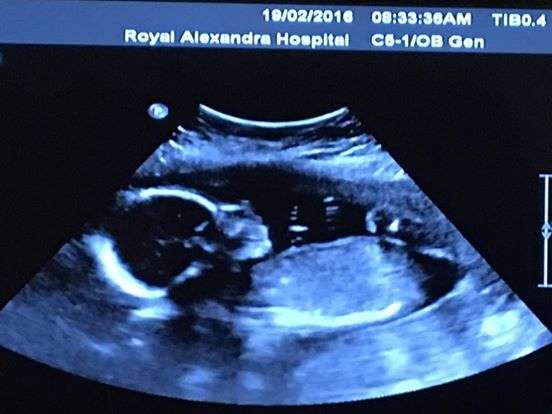

ԼԱՅՖԵրբ կանադացի ամուսիններ Թիմ և Բեթանի Ուեբները գնացել են ուլտրաձայնային հետազոտության, պարզվել է՝ Բեթանին հղի է եղել միաժամանակ չորս աղջիկներով:

Ու թեև այդ լուրը ցնցել է զույգին, նրանք արագ հարմարվել են և սկսել պատրաստվել երեխաների ծնունդին: Փոքրիկները կեսարյան հատումով են ծնվել: Աղջիկներին անվանել են Էբիգեյլ, Գրեյս, Էմիլի և Մաքքայլան:

Աղջիկները չափազանց փոքր են եղել, ուստի կյանքի առաջին շաբաթները հիվանդանոցում են անցկացրել:

Նրանց քաշը 1 կիլոգրամից պակաս է եղել: Բոլոր աղջիկները երկվորյակ են եղել:

Ըստ գենետիկների՝ այդպիսի բան լինում է 15 միլիոնից մեկի մոտ: